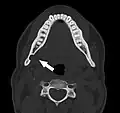

Stafne bone cavity seen on coronal CT

Stafne bone cavity seen on coronal CT -

Stafne bone cavity seen on axial CT

Stafne bone cavity seen on axial CT